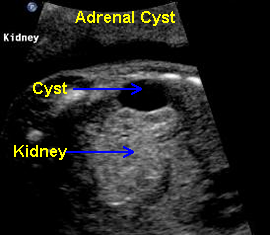

Adrenal Cyst, 19 6/7 weeks

Above. Oblique view. Cystic structure, superior and extrinsic to the right kidney of adrenal origin.

Above. Longitudinal view. Right sided cyst, superior and extrinsic to the kidney.

Above. Transverse view. Note relationship of the kidney to the adrenal cyst which measures 1.7 X 1.3 cm.